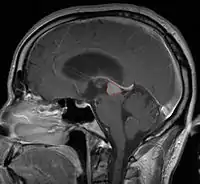

Pineal Gland Tumors

- Determined by the spatial anatomy and direction of growth

- Obstruction of aquaduct: hydrocephalus presenting as headaches, nausea, vomiting

- Compromise of superior colliculus: vertical gaze palsy, pupillary and oculomotor nerve paresis (Parinaud syndrome)

- Progressive growth: cranial nerve neuropathies, hypothalamic dysfunction

Treatment Overview

- Work-up includes MRI, CSF, serum markers for bHCG and AFP

- Tissue diagnosis is critical, since management varies significantly based on pathology

- Stereotactic pineal gland biopsy

- Open surgery (typically not favored since only few tumors are amenable to complete resection, many are chemo-RT sensitive, and there is a real risk of worsening visual deficits)

- CSF diversion may be necessary in patients symptomatic from obstructing hydrocephalus, although if open surgery is done, may not be necessary